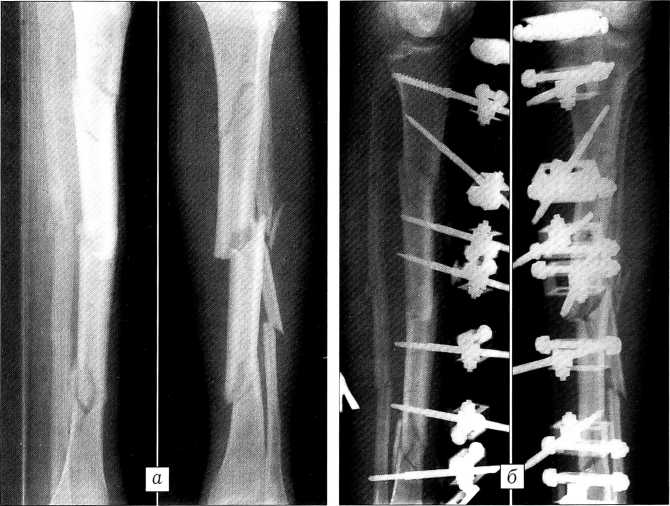

Больной Д . ,39 лет, доставлен в стационар через 5 ч после получения травмы (сбит автомашиной при переходе улицы). По результатам клинического и рентгенологического обследования диагностированы открытые оскольчатые переломы диафиза костей обеих голеней со смещением отломков типа С1 (рис. 3, а, в); травматический шок II степени. В день поступления произведен остеосинтез переломов обеих голеней стержневыми аппаратами с «плавающими» фиксаторами стержней (рис. 3, б, г). Через проколы кожи и мягких тканей длиной до 1 см по внутренней поверхности голеней введено по три стержня в проксимальный и дистальный отломки. После стабилизации проксимальных стержней в аппаратах выполнены закрытая репозиция с помощью съемных рукояток и фиксация дистальных стержней.

Рис. 3. Рентгенограммы больного Д.: а — правая голень при поступлении, б — после операции; в — левая голень при поступлении, г — после операции.

Пациент выписан на амбулаторное лечение через 15 дней. К этому времени ходил без дополнительных средств опоры, объем движений при сгибании в левом коленном суставе составлял 0-100°, в правом — 0-120° (рис. 4, а). После сращения перелома и демонтажа аппаратов объем движений в обоих коленных суставах восстановлен полностью (рис. 4, б).